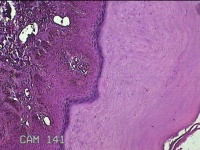

左侧腰部皮肤息肉组织

性别

男

年龄

40岁

临床诊断

皮肤和皮下组织良性脂肪瘤样肿瘤,其他部位的

一般病史

发现左侧腰部皮肤息肉组织5年余。

标本名称

大体所见

灰白暗红色息肉样组织1.7x1.3x0.3cm一块,表面糜烂,切面灰白暗红色,质软。